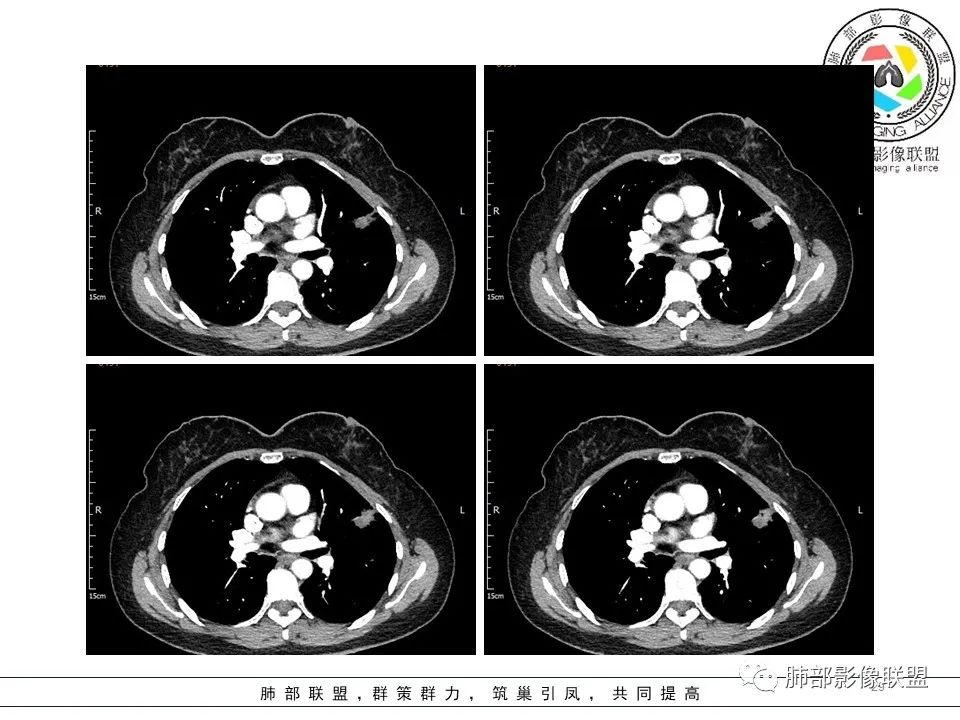

3.病灶实性密度区强化明显,这有助于我们区分一些其他类似病灶,如结核灶等! 医学百科网 | YxBaike.Com

结合临床,应当高度怀疑浸润性肺腺癌!